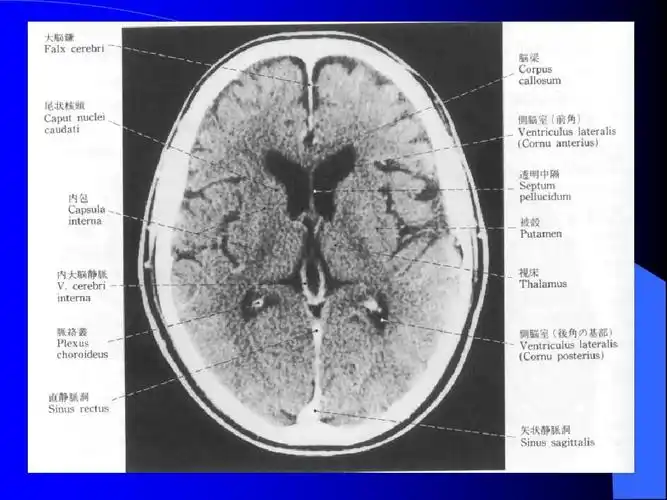

脑池的断面解剖图ppt